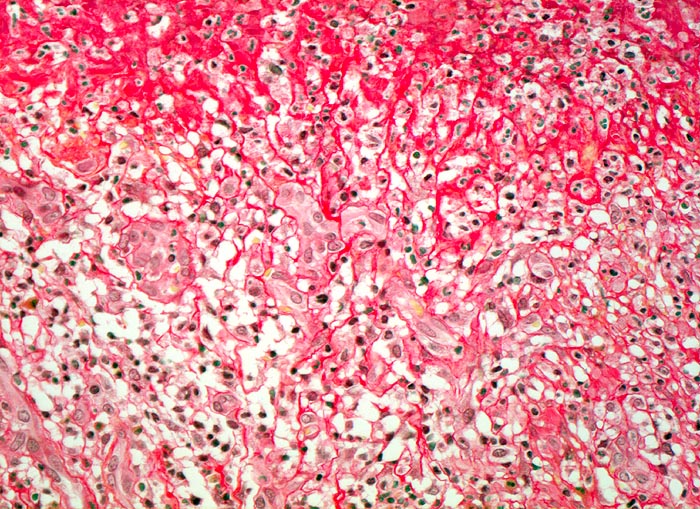

Magenulkus: Quellungsfibrinoid und Granulationsgewebe

Oben im Bild die verquollenen orangeroten Kollagenfasern durchsetzt von neutrophilen Granulozyten. Das nekrotische Kollagen wird von gefässreichem Granulationsgewebe organisiert (unten im Bild).

Peptisches präpylorisches Ulkus bei langjähriger Therapie mit nichtsteroidalen Antirheumatika bei chronischer Polyarthritis. Notfallmässige Gastrektomie wegen massiver Ulkusblutung.